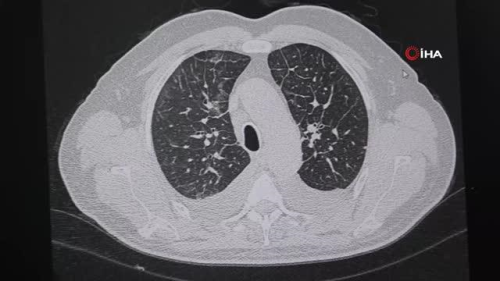

BURSA Göğüs Hastalıkları Uzmanı Dr. İbrahim Ocak, son dönemde sosyal medyadan görerek uygulanan su diyeti gibi diyetlerin ölüme davetiye çıkardığını söyledi. Diyetisyen Meltem Yavaş ise diyetlerin parmak izi gibi kişiye özel olduğunun unutulmaması gerektiğini ifade etti. Bursa'da eşinin uyguladığı su diyetini kendi de uygulamak isteyen kişi, hızlı kilo verdiğine sevinirken hayatını kaybediyordu. 2 ay önce başladığı diyetin kilo haricinde vücudundaki değişimleri fark edemeyen kişi, fenalaşması üzerine hastaneye kaldırıldı. Yapılan incelemelerin ardından tedaviye başlanan hasta, hayati tehlikeyi atlattı. Hastaya müdahaleyi yapan VM Medical Park Bursa Hastanesi Göğüs Hastalıkları Uzmanı Dr. İbrahim Ocak, "Son bir hafta içinde iki hastam acil bölümünden geldi. Biri yaygın kemik ve eklem ağrıları, halsizlik, yoğun kırgınlık, kandaki oksijen yüzdesi yüzde 74'lere kadar inmiş bir haldeydi. Acilde hastayı değerlendirdikten sonra tomografi ve kan tahlili yaptık. Kan tahlillerinde ürekratin elektrolit dengesinin çok değişmiş olduğunu gördük. Neredeyse tüm vücudunun elektrolitleri değişmiş ve zararlı düzeye gelmişti. Çektiğimiz tomografide de akciğerde ploraze dediğimiz sıvı birikmesi olmuş, kalp enzim değerleri artmış ve enfeksiyon değerleri yükselmişti. Niçin böyle olduğunu öğrenmeye çalışırken, hasta yaklaşık 2 aydır su diyeti yaptığını söyledi. Nasıl uyguladığını sorduğumda ise, 'Su içiyorduk. Günde 3 öğün, maydanoz, dereotu, roka gibi sadece sebze ağırlıklı beslendik' dedi. Hastamızı yatırdık, tedavisine başladık. Diyetini kestik ve normal beslenmeye geçtik. 3-4 gün içerisinde toparladı. Durumu şimdi daha iyi. Bende su diyetinin sosyal medyada reklamını görmüştüm. Hatta kendi hesabımda 'bu şarlatanlıktır, bu doğru değildir' yazdım. Orada eleştirilere de uğradım. Ama hala aynı şeyi söylüyorum" dedi. "Her hastama diyeti bende tavsiye ediyorum" Su diyetinde bireylere sadece su içirip sebze ağırlıklı beslenme yapıldığını ifade eden Uzm. Dr. Ocak, "Bu 2, 3 veya 5 ay sürebiliyor. Bazı kişilerde olumsuz bir durum gözükmeyebiliyor. Tabi ki aç kalmaya bağlı insanlar yoğun kilo verebiliyor. Diyetisyenlik bölümü diye bir gerçek var. Sadece bu işe bakıyorlar. Diyet sanıldığı gibi kolay bir şey değildir. Muayene yapmadan, incelemeden rastgele diyet uygulanması doğru değildir" diye konuştu. Diyetisyen Meltem Yavaş ise, "Su diyetleri veya farklı isimlerle anılan diyetleri sosyal medyada sıkça duymaktayız. Fakat sağlıklı zayıflamada bunların yeri katiyen yoktur. Sağlıklı zayıflama diyetlerinde bizler kişinin ihtiyaçlarına göre matematiksel hesaplamalarla kişiye göre diyet listeleri oluşturuyoruz. Herkesin diyeti aslında 'parmak izi' gibi diyebiliriz. Yapılan su diyetleri, lahana diyetleri kişinin vücudunda ciddi rahatsızlıklara sebep olabilir. Kısa sürede vitamin mineral yetersizliklerine bağlı aslında katlanılabilir rahatsızlıklar olsa da, uzun vadede organ hasarlarına kadar yol açabilir. Geri dönüşü olmayan sorunlarla karşılaşılabiliyor. Örneklerini çok fazla görüyoruz. Çevremizde çok uçuk fiyatlarla hiç alakası olmayan, beslenmeyle ilgili hiç eğitim almamış kişiler, kendisine inana kişilere aslında sıvı besinler, detox programları uyguluyorlar. Biz her defasında söylüyoruz, katiyen kullanılmamalı" dedi.